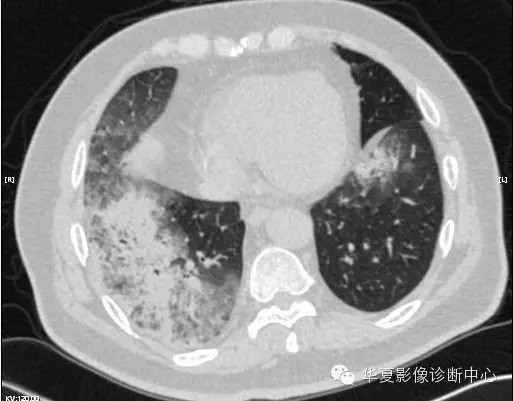

【病例学习】甲型H7N9禽流感一例

男性 63

发热咳嗽5天

2013-4-5拍片示右肺实变,收入院,追问病史,发病期间肌肉酸痛,头痛,无腹痛腹泻,无明显胸闷气急,无意识改变。有高血压病史,无其它病史。

2013-4-7CT进一步检查。

最终诊断:H7N9。